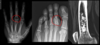

El desgarro del manguito rotador es común en edad:

A

Edad avanzada